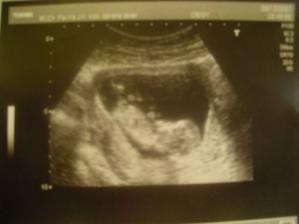

Tak máme velký utz za sebou, byl to krásný zážitek, náš bobíček ve 21+1 měří 25cm, váží 400g a byl úplně úžasný. Všechny orgány máme v pořádku. Pohlaví bylo vidět, ale s taťkou jsme vydrželi a těšíme se až se nám mimísek ukáže v plné kráse.🙂

4.2.2007 velký genetický utz-byl to krásný zážitek, náš bobíček ve 22+5 měří 25cm, váží 400g a byl úplně úžasný. Všechny orgány máme v pořádku. Pohlaví bylo vidět, ale s taťkou jsme vydrželi a těšíme se až se nám mimísek ukáže v plné kráse.🙂